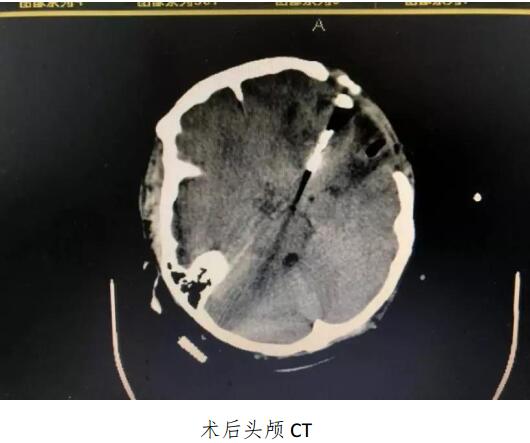

成人导航 成功开展颅内动脉瘤夹闭术及脑血管造影动脉瘤栓塞术